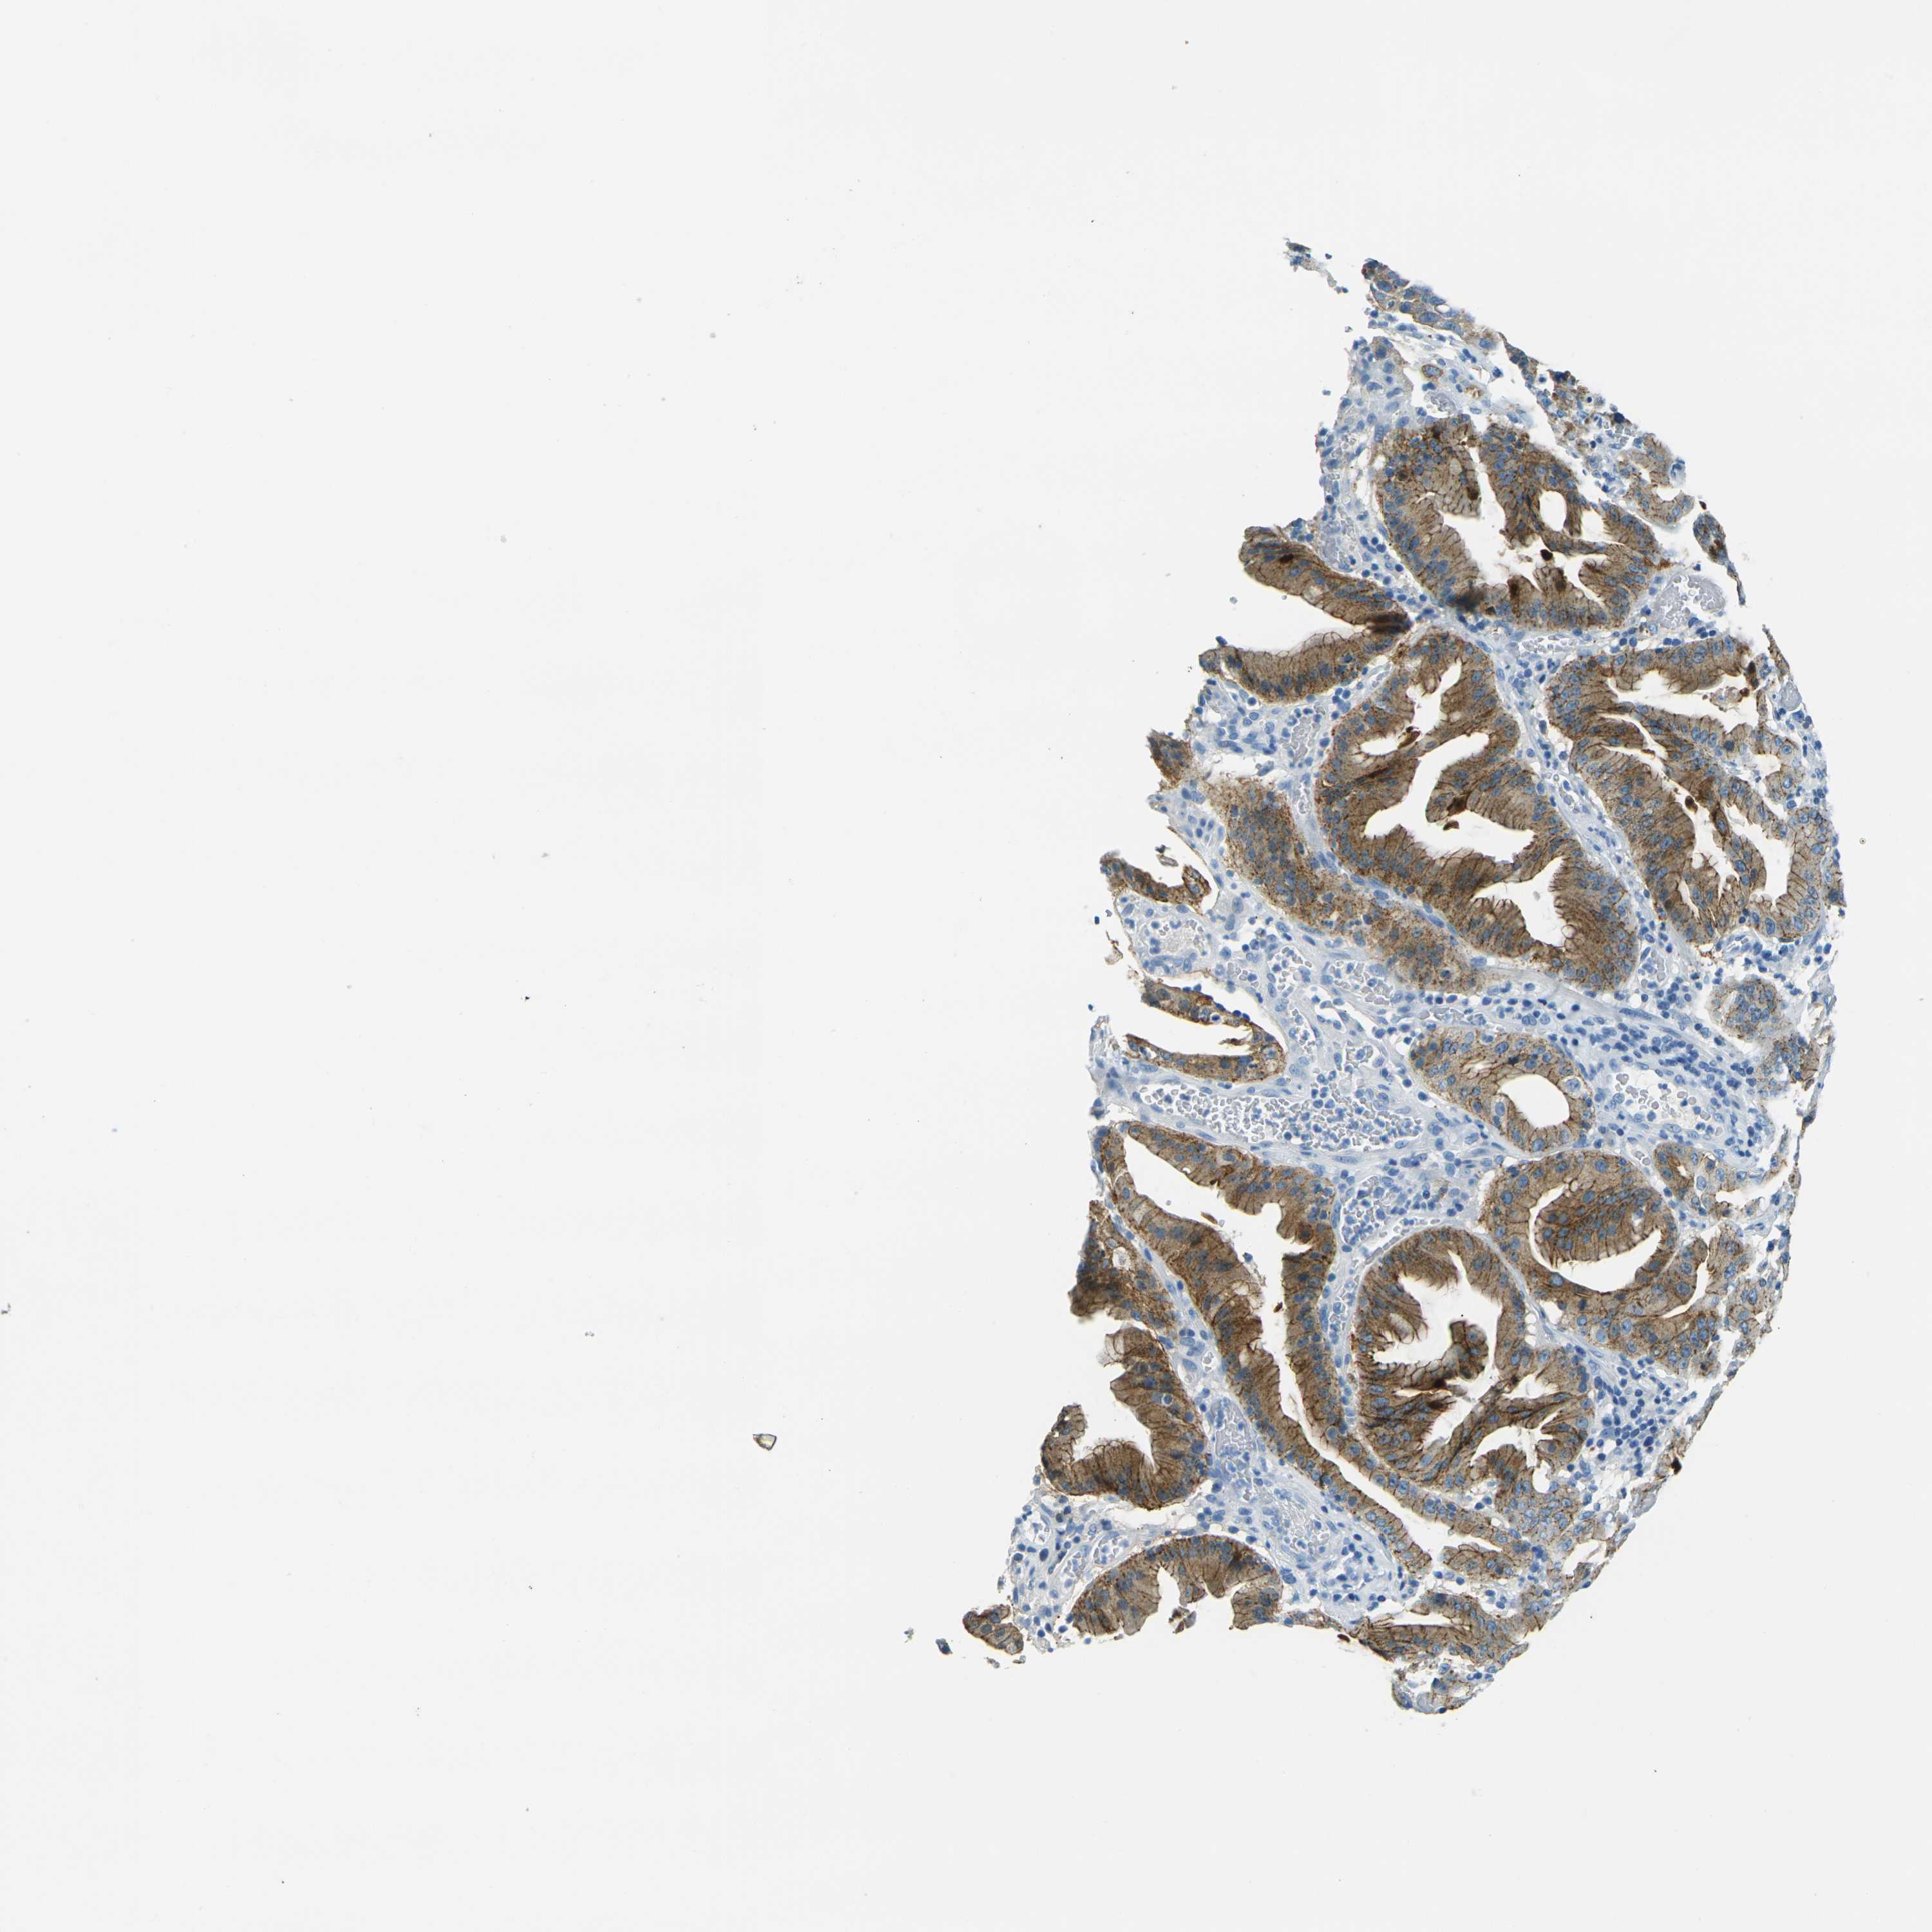

STOMACH CANCER - Protein expressioni

A mouse-over function shows sample information and annotation data. Click on an image to view it in a full screen mode. Samples can be filtered based on level of antibody staining by selecting one or several of the following categories: high, medium, low and not detected. The assay and annotation is described here.

Note that samples used for immunohistochemistry by the Human Protein Atlas do not correspond to samples in the TCGA dataset.

Antibody stainingi

Antibody staining in the annotated cell types in the current human tissue is reported as not detected, low, medium, or high, based on conventional immunohistochemistry profiling in selected tissues. This score is based on the combination of the staining intensity and fraction of stained cells.

Each image is clickable and will lead to virtual microscopy that enables deeper exploration of all samples and also displays staining intensity scores, fraction scores and subcellular localization as well as patient and tissue information for each sample.

HPA005933

CAB013075

CAB068212

CAB068213

CAB068214

Adenocarcinoma, NOS

Adenocarcinoma, High grade